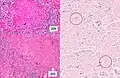

Gross pathology of the lung, spleen and kidney, showing micronodules (1–4 mm in diameter) which resemble millet seeds -

Histopathology, showing epithelioid granulomas with multinucleated giant cells and acid-fast bacilli